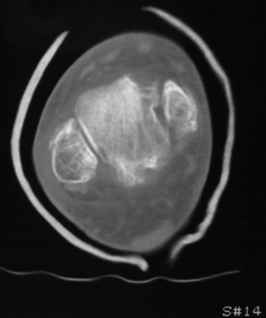

Остеопороз (продолжение 3) - данные КТ

Продолжая тему представляю данные КТ нашей пациентки.